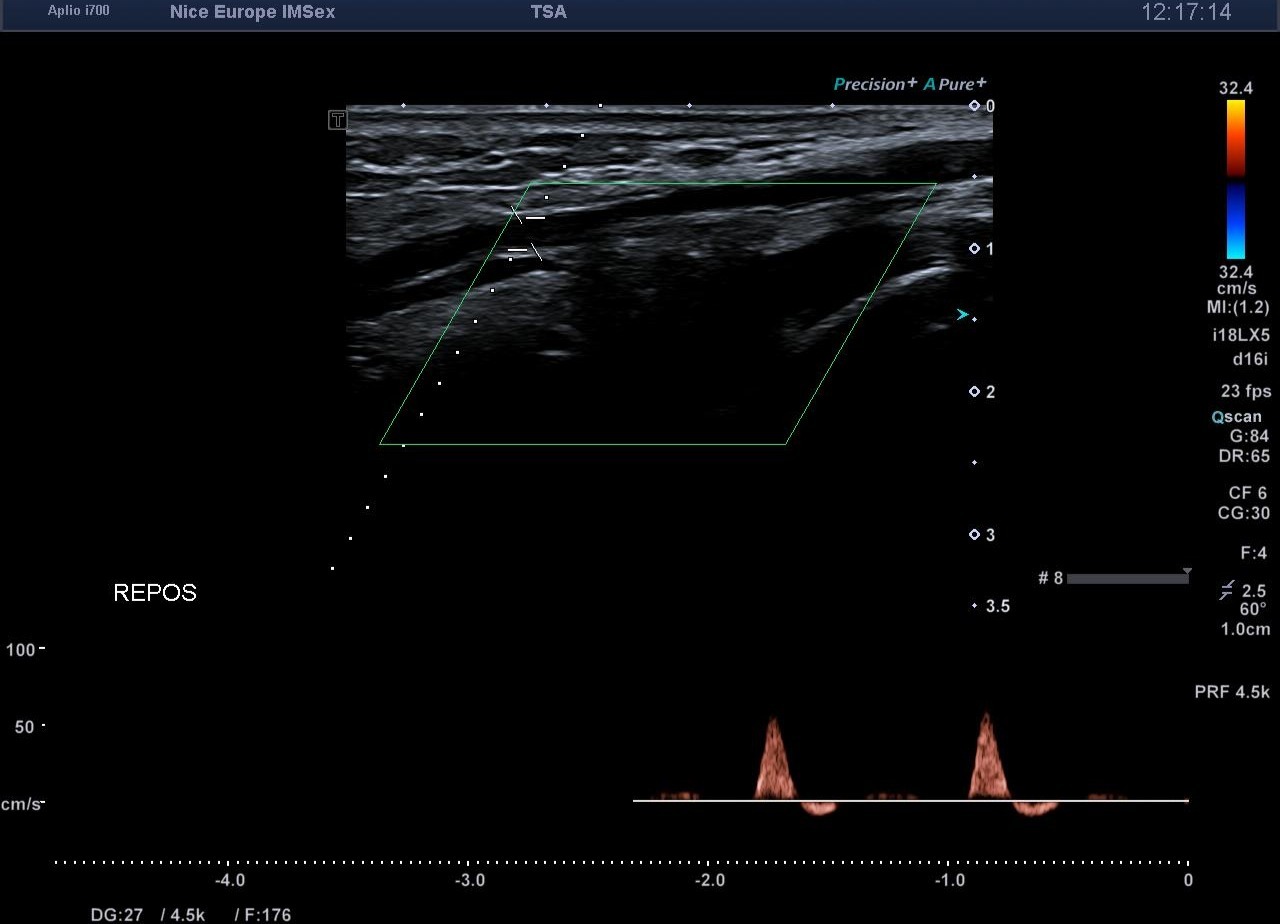

Devant ce morphotype athlétique et la négativité de l'examen statique, un test de provocation par échographie dynamique est entrepris pour rechercher un syndrome de l'artère poplitée piégée (ou piège poplité). Lors d’une manœuvre de flexion plantaire contrariée (mise en tension soutenue des muscles de la loge postérieure contre résistance), on objective en temps réel :

1. 1. Une compression extrinsèque majeure de l’artère poplitée par les chefs musculaires gastrocnémiens.

2. 2. Une occlusion artérielle complète (diastolique et systolique) au point de compression.

3. 3. Une abolition du flux artériel distal.